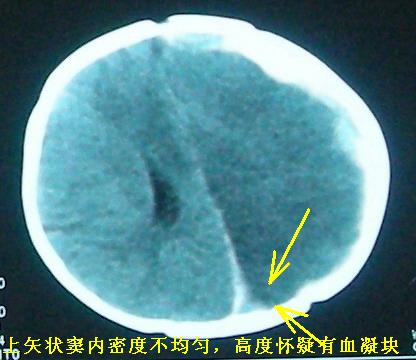

硬膜下出血、蛛网膜下腔出血(至于病因,可能与外伤有关,慢性出血的可能性比较大。但应该不是产伤所致?)--上矢状窦内血凝块 --静脉回流不畅或受阻--进而形成左侧大面积水肿和梗塞。临床有高热,感染所致 脓栓栓塞血管不排除,但它不好解释为什么会有硬膜下出血。

[br][br] 硬膜下出血、蛛网膜下腔出血(至于病因,可能与外伤有关,慢性出血的可能性比较大。但应该不是产伤所致?)--上矢状窦内血凝块 --静脉回流不畅或受阻--进而形成左侧大面积水肿和梗塞。临床有高热,感染所致 脓栓栓塞血管不排除,但它不好解释为什么会有硬膜下出血。[br] 一点儿浅见,请老师们别见笑。渴盼老师们更多的精彩评论![br]